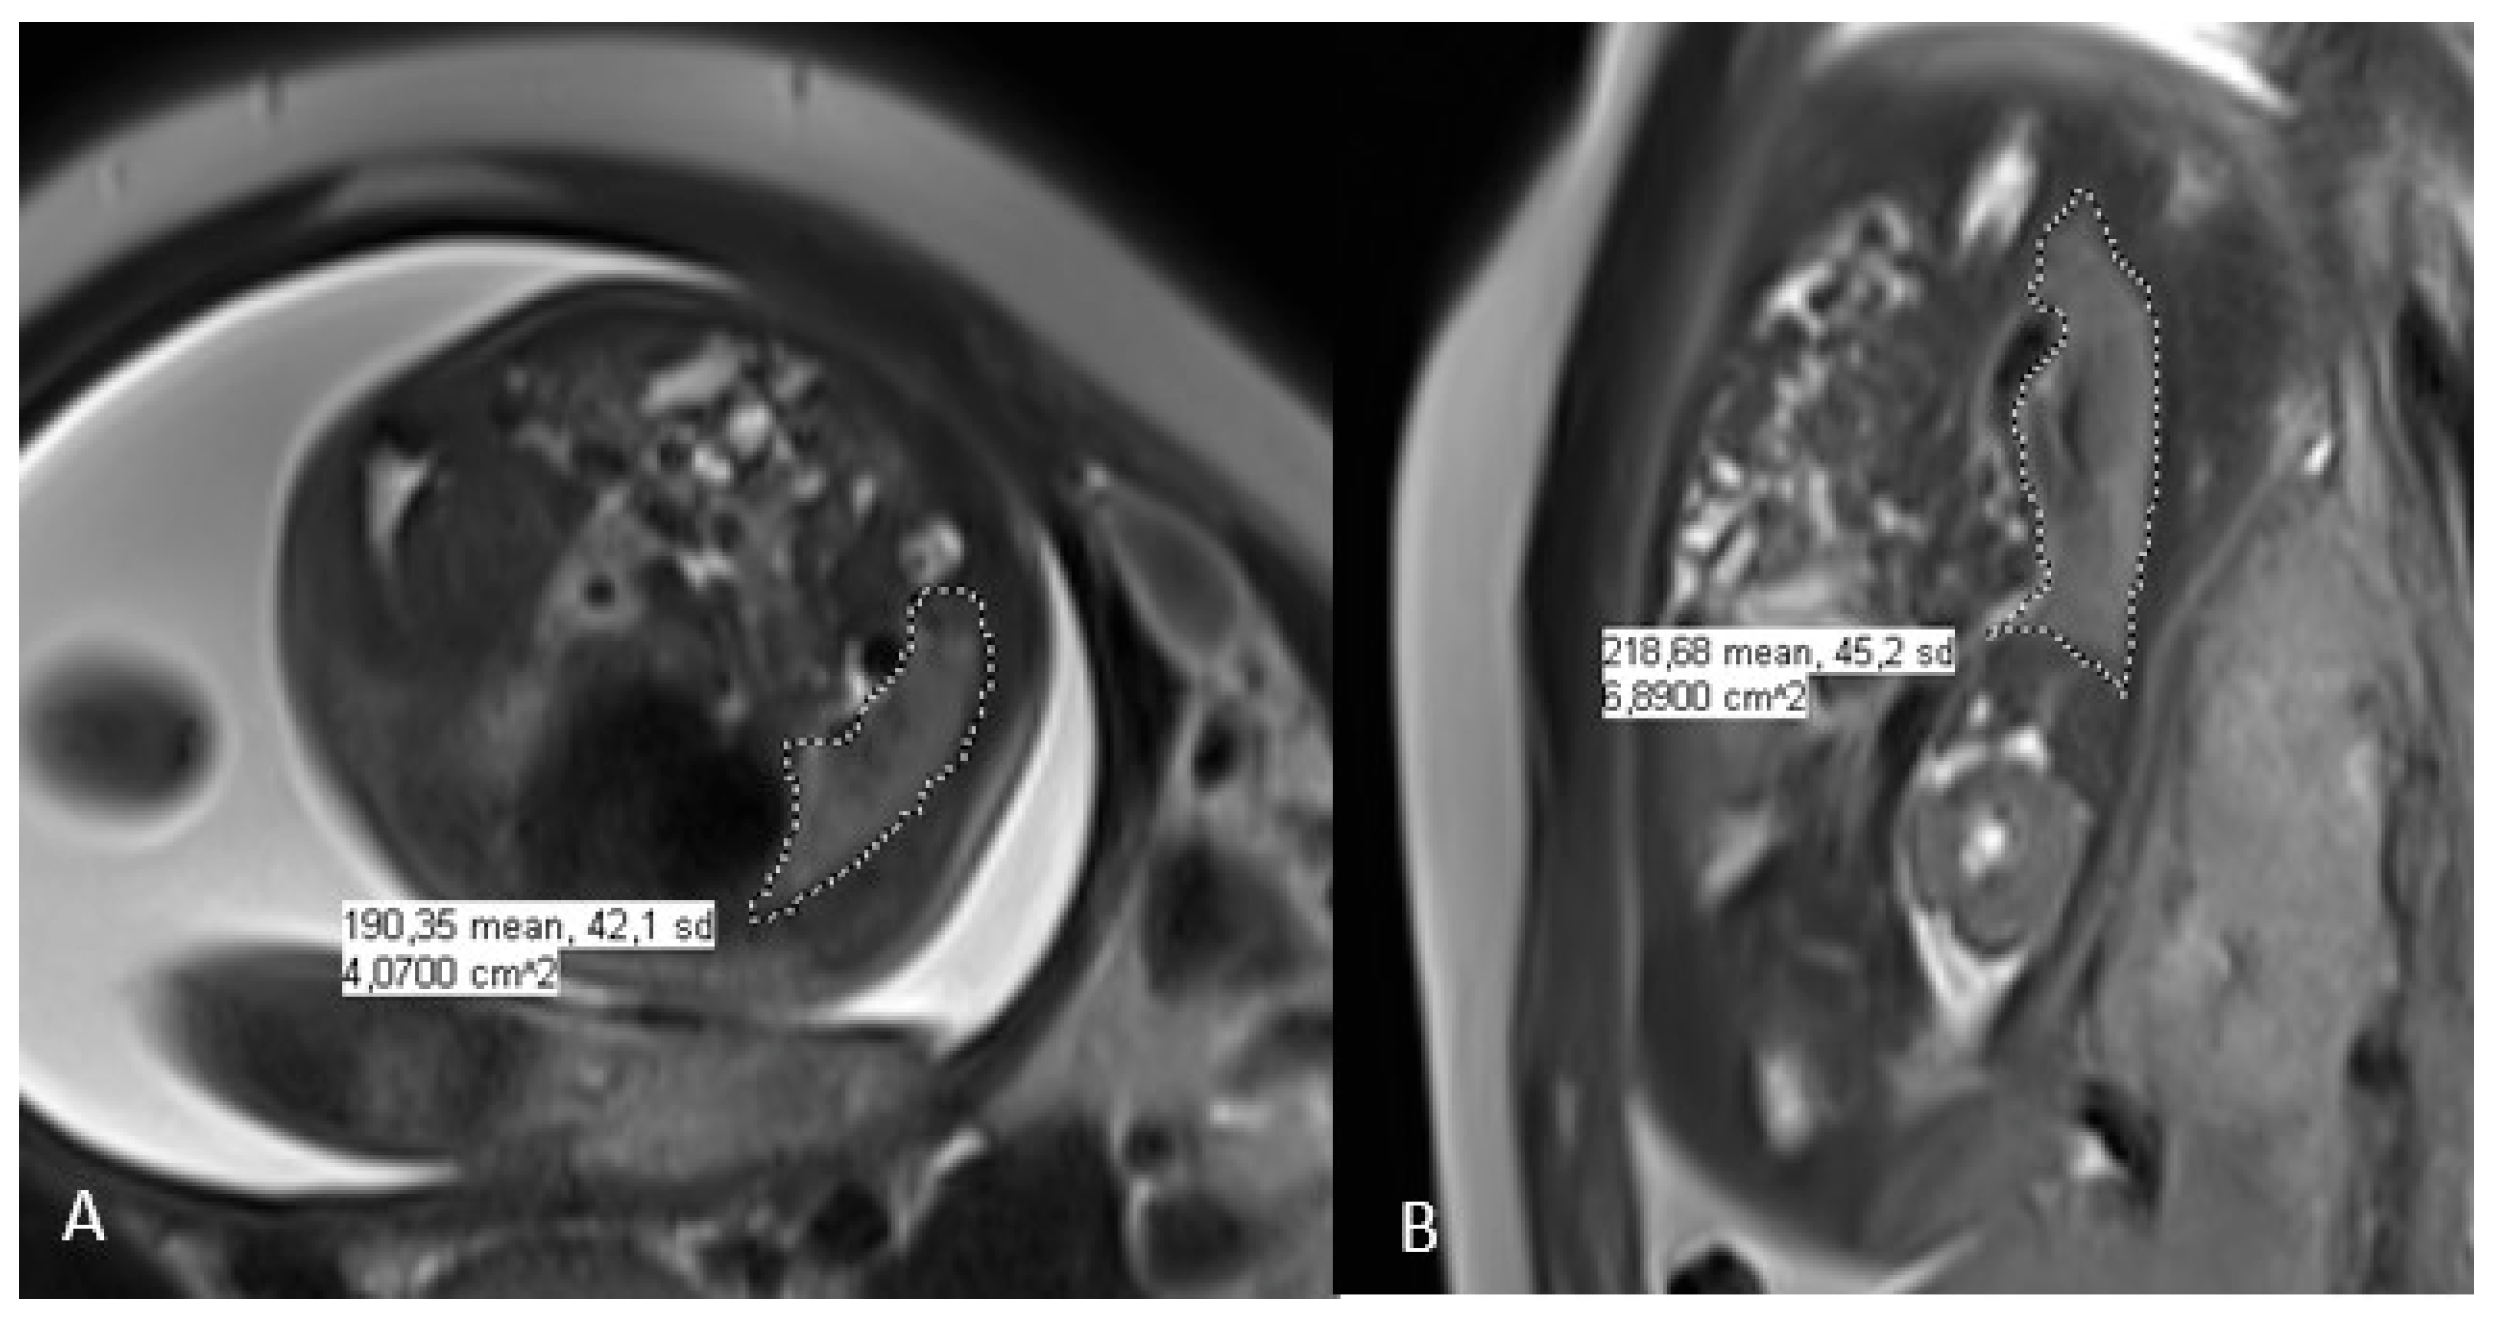

As part of the follow-up performed at the CDH reference center, one or two fetal MRI imaging scans were performed after the prenatal diagnosis of CDH: the first between 26 and 28 weeks and the second between 30 and 32 weeks of gestation. In cases of two MRIs, we used the first images. The fetal MRIs were performed using a Philips Ingenia 3 TESLA MRI imaging scanner. No premedication was given, and the mother was placed in supine position. The examination time was about 30 min. The protocol included three T2 planes (TE 70) and T1-weighted sequences in the axial and sagittal planes. The T2-weighted images were obtained using a single-shot half-Fourier TSE sequence in the orthogonal transverse coronal and sagittal planes according to the fetal orientation. The sequences affected by fetal movements were repeated. The cutting thickness was 4 mm. Measurements were performed by two radiologists qualified for this evaluation using PACS software (IntelliSpace PACS 4.4, Philips, Amsterdam, The Netherlands) using a contour (freehand region of interest) cut. The contouring was performed on the sequence that allowed the best visualization, either coronal or sagittal (Figure 1). The o/e FLV was calculated as a function of gestational age using the Rypens formula and is expressed as a percentage [6].

Figure 1.

MRI assessment of the right CDH allows the calculation of fetal lung volume (FLV); (A): axial and (B): coronal.